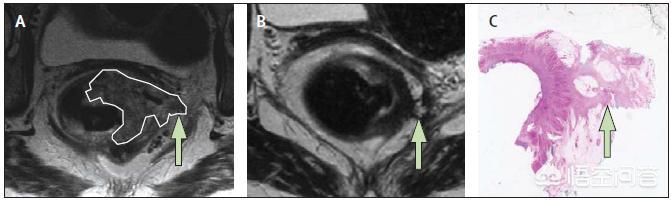

术前放疗能够降低肿瘤的负荷,使不能手术的患者,转变为可手术的患者,减少局部复发率。下面这张图是一个直肠癌的患者,A图为放疗之前的MRI图像,肿瘤非常大,已经浸透肠壁了;经过放疗后,肿瘤明显缩小(图-B);做手术后,将切下来的组织送去活检,显微镜下没有发现癌细胞,达到了完全缓解,通过放疗就治愈了直肠癌。